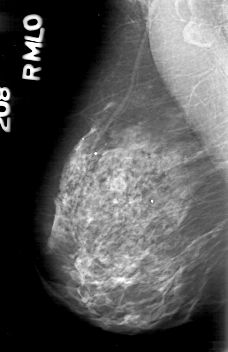

D_4164_1.RIGHT_MLO

RIGHT_MLO LINES 5266 PIXELS_PER_LINE 3406 BITS_PER_PIXEL 12 RESOLUTION 43.5 NON_OVERLAY